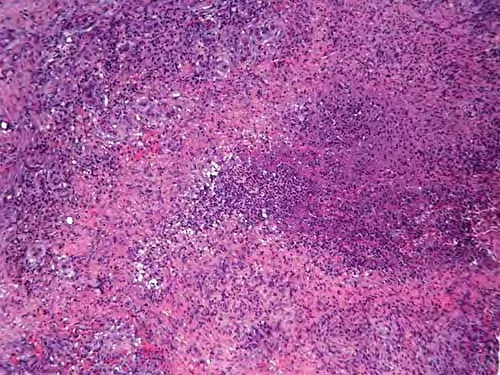

pathologic examination of tissue can reveal tuberculoid, palisading, and sarcoidlike granulomas; a diffuse infiltrate of histiocytic foamy cells; acute and chronic panniculitis; nonspecific chronic inflammation; cutaneous abscesses; suppurative granulomas; and necrotizing folliculitis. Suppurative granulomas are the most characteristic feature in skin biopsy specimens from cutaneous atypical mycobacteria infections. The evolution of the disease and the immunologic status of the host may explain this spectrum of morphologic changes.

Some authorities note severe inflammatory lesions involved with the dermis and the hypodermis; these can have 3 main histopathologic patterns: granulomatous nodular or diffuse inflammation with mixed granulomas, prevailing abscesses with mild granulomatous reaction, and deep dermal and subcutaneous granulomatous inflammation with no neutrophil component.